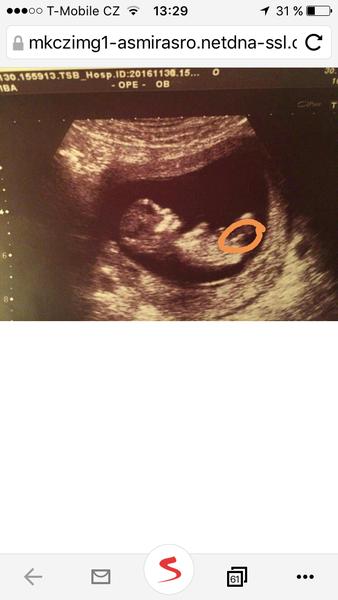

Je to holčička nebo chlapeček? Foto ultrazvuku

tak musim rict, ze u nas se na 1. screeningu lekari trefili i napodruhé.. poprvé to byl kluk, ted podruhe holka..... fotky uz jsem davala...